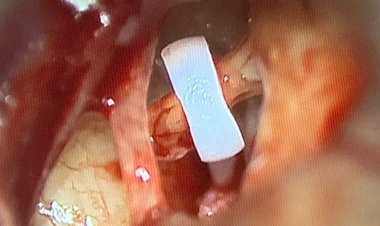

Insulinomas are rare and elusive pancreatic tumours that frequently evade routine...